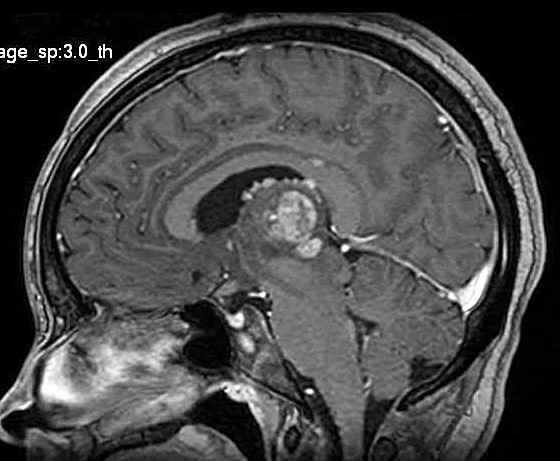

| Fem. 17a. |

| Nódulo sólido homogêneo preenchendo o III ventrículo, com limites precisos, com hipossinal em T1 e hipersinal em T2 e FLAIR, que se impregna por contraste paramagnético. Lesão menor implantada no assoalho do IV ventrículo provavelmente representa disseminação por via liquórica. |

| F. 17a. Tumor teratóide rabdóide atípico de III ventrículo. RM | HE | VIM, GFAP | HHF35, desmina, 1A4 | AE1AE3, EMA |